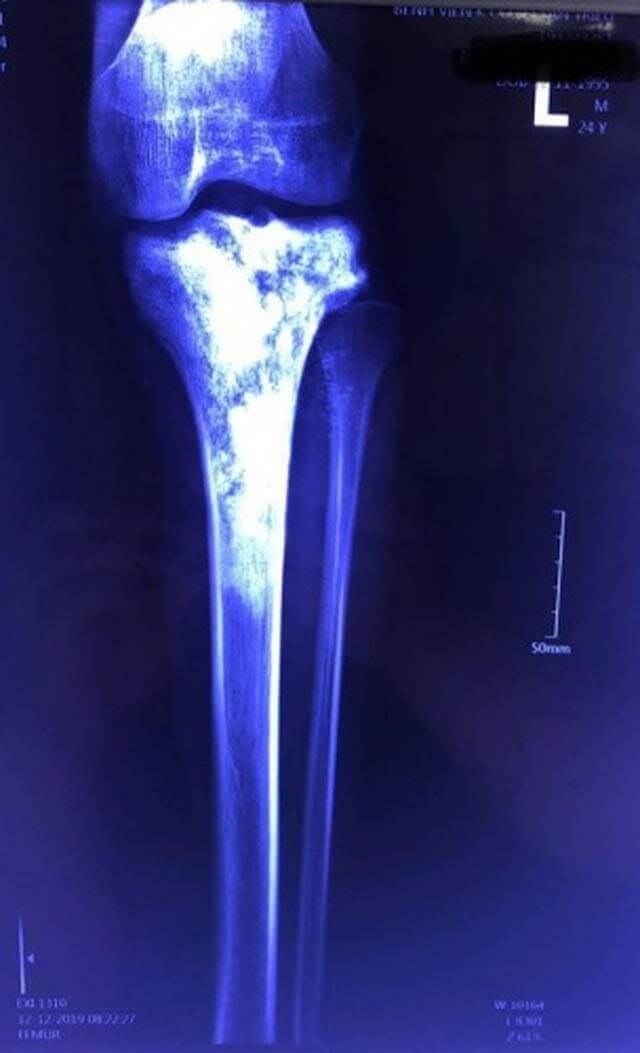

Hình ảnh khối ung thư xương chày trên phim X-quang

Bệnh nhân là anh Nguyễn Văn H, 24 tuổi. Khoảng 1 năm nay, bệnh nhân thỉnh thoảng xuất hiện đau âm ỉ vùng cẳng chân trái. Gần đây các cơn đau đến nhiều hơn, cảm giác như kiến bò trong xương rất khó chịu. Bệnh nhân thường xuyên gần như không ngủ được, phải dùng đến nhiều loại giảm đau kết hợp và thuốc ngủ.

Bệnh nhân đến khám tại Bệnh viện K Trung ương (Hà Nội) và được chẩn đoán ung thư xương (Chondrosarcoma).

Với loại tổn thương này hóa, xạ trị rất ít tác dụng. Phẫu thuật là lựa chọn duy nhất. Tuy nhiên mức độ lan rộng tổn thương tại xương chày là rất lớn. Để loại bỏ triệt căn khối u cần phải cắt toàn bộ 2/3 trên xương chày. Do đó bệnh nhân đối diện nguy cơ phải cắt cụt 1/3 dưới xương đùi.